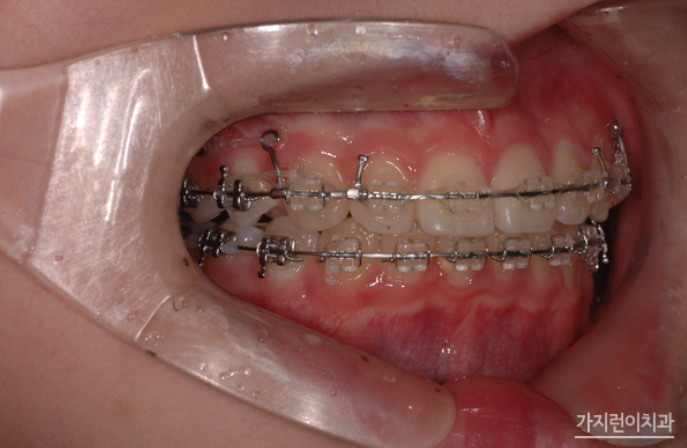

교정용 헤드기어와 스크류를 적극 활용한 케이스라고 할 수 있는데요. 헤드기어의 경우 통상적으로 하루에 12시간 이상 착용을 해야 하기 때문에 주로 취침 시 착용할 것을 권고하는데요. 임의대로 시간을 조절해 착용해서는 안 됩니다. 제대로 시간을 지키지 않을 시 어금니가 이동하지 않아 충분한 공간 확보가 어려워져 결국 발치가 할 수도 있는데요. 때문에 치아의 이동양상에 따라 치과를 방문해 팽팽함을 유지해야 합니다. 여기에 뻐드러진 앞니가 제자리를 찾을 수 있도록 미니스크류를 식립하여 위턱 전체 치열을 후방으로 이동시켰는데요.